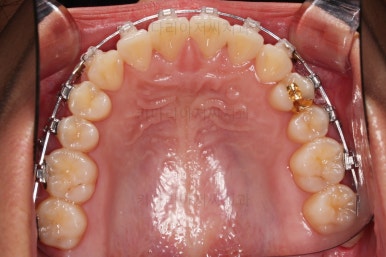

장치를 부착했는데요.

윗니는 웃을 때 더 많이 보이기 때문에 세라믹 장치를 선택하셨고, 아랫니는 거의 안보이는 타입이셔서 메탈장치로 부착을 했습니다.

위아래 둘 다 자가결찰 장치였고요.

동일 회사의 장치였으며 단지 재질만 메탈이냐 세라믹이냐의 차이가 있었던거죠.

이렇게 위아래는 설측이든 뭐든 메탈이든 세라믹이든 마음대로 섞을 수 있습니다.

윗니의 배열과 위치는 거의 완성이 되었고요.

아래는 아직 틈이 많이 보이죠.

어금니를 부산치아교정 통해 계속 앞으로 당겨줍니다.